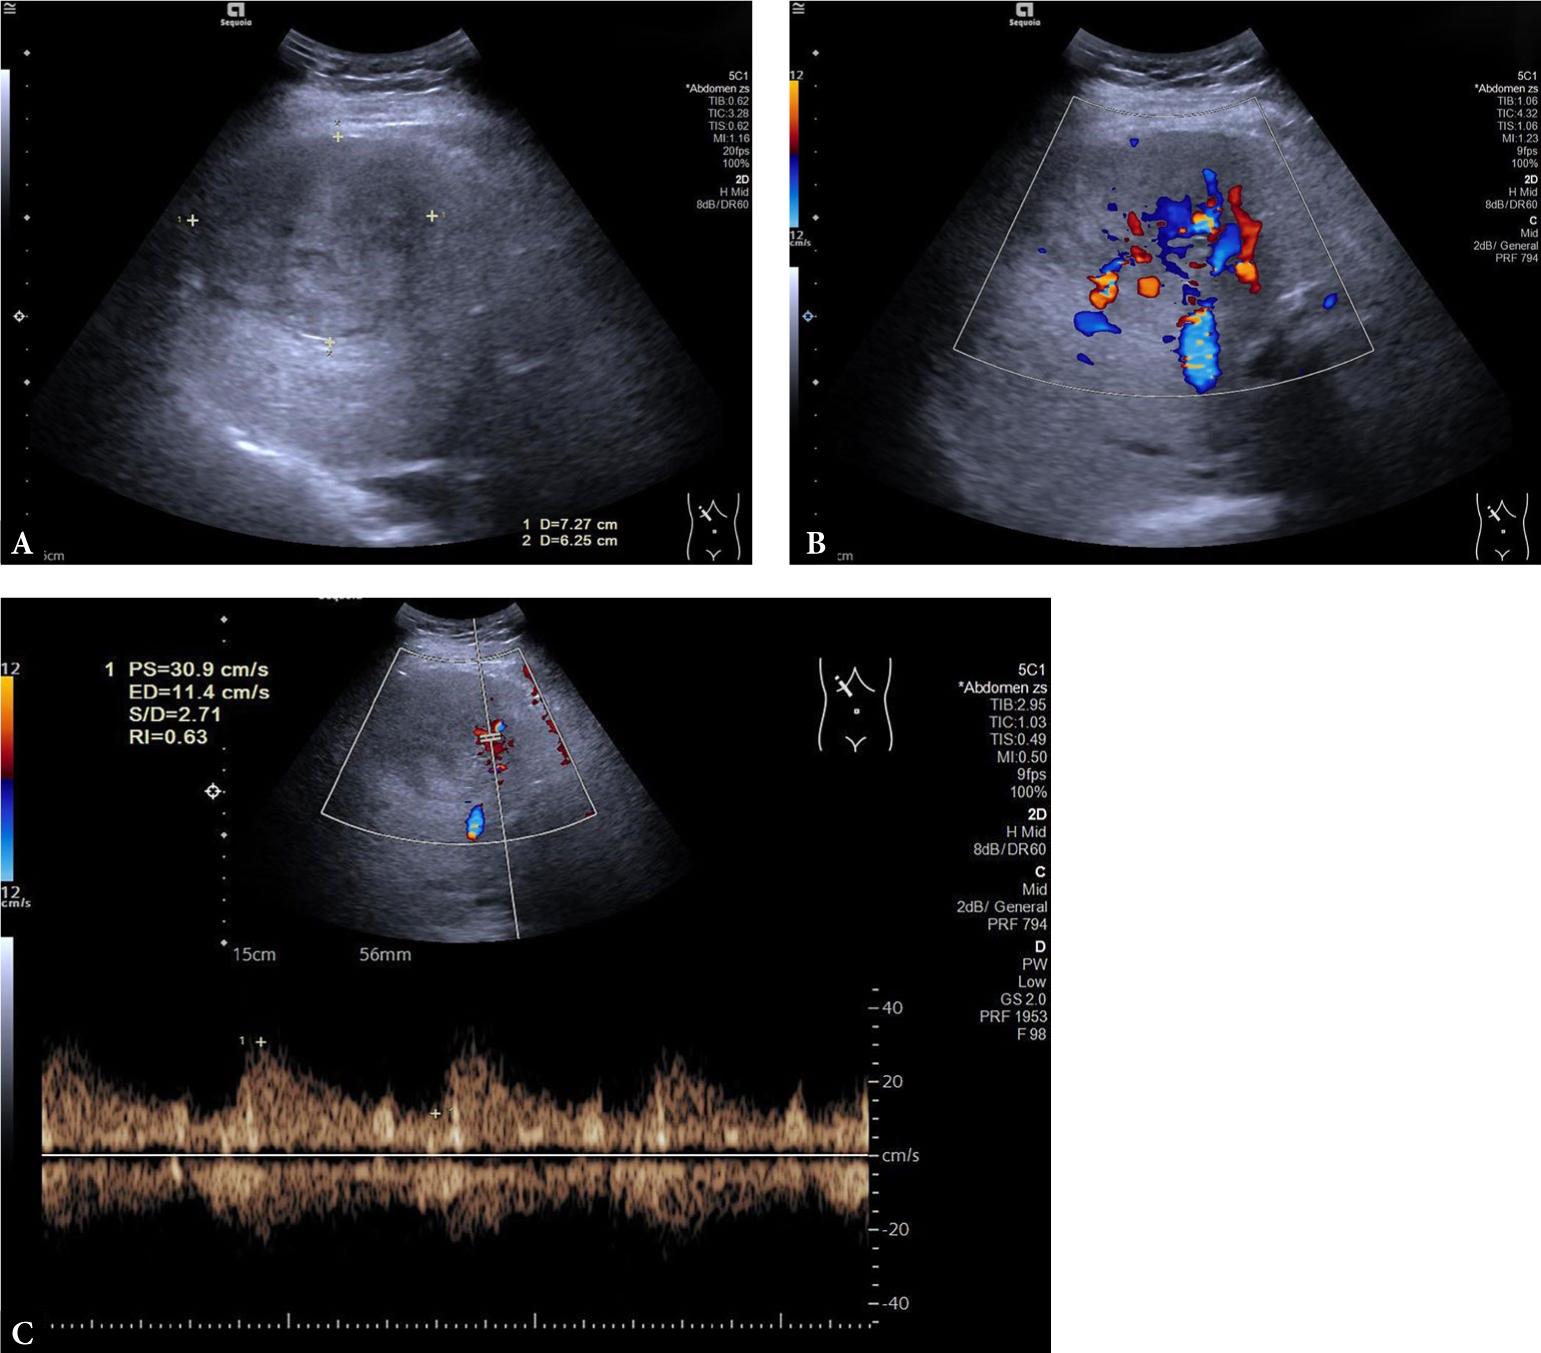

Fig. 2.